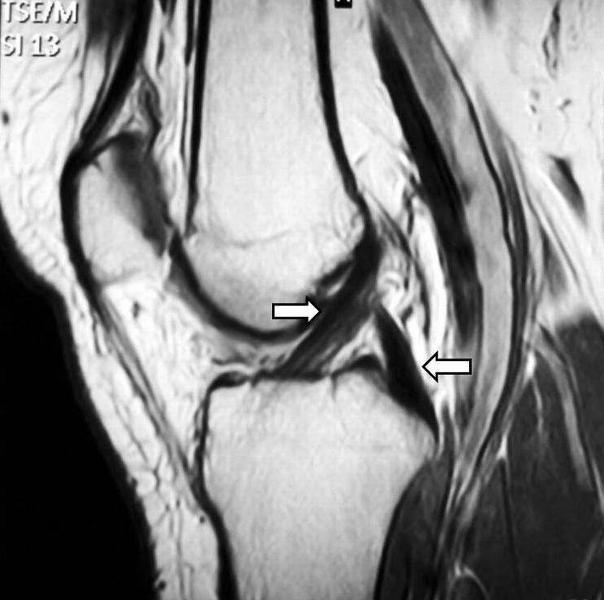

LCM, LCL, LCA, LCP